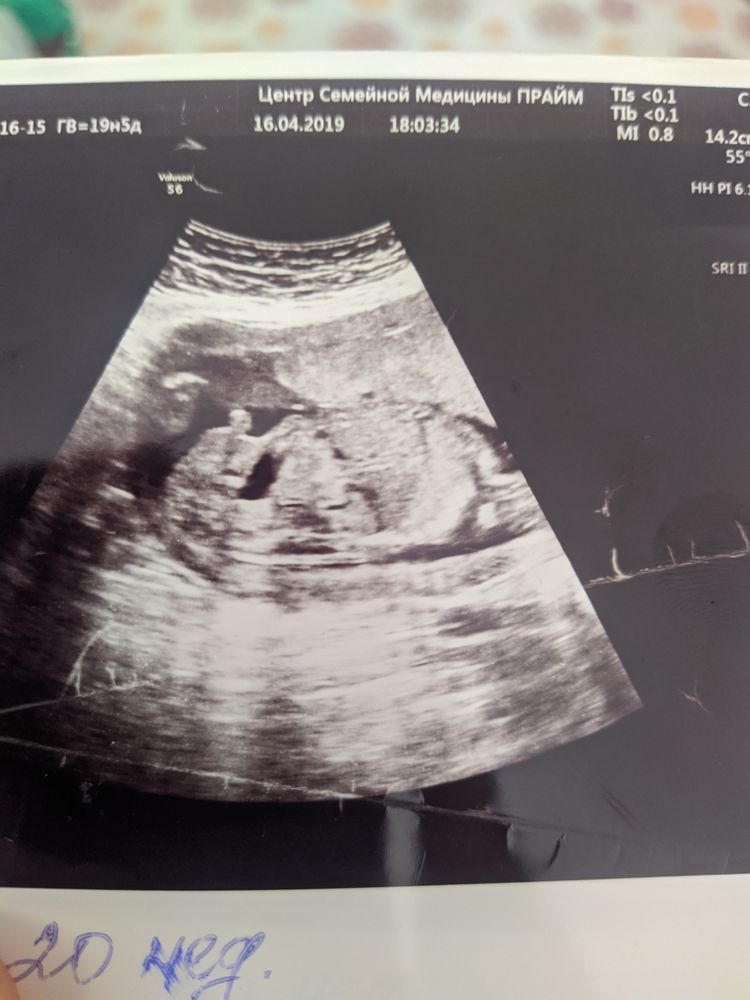

Помогите определить пол ребенка

У меня на первом скрининге прям один в один такой же бугорок под таким же углом. УЗИстка сказала, что хоть и угол «девочкин» размер имеет большее значение, а размерчик бугорка больше мальчиковый)) жду вот тоже следующего УЗИ через пару недель уже окончательно увидеть кто там